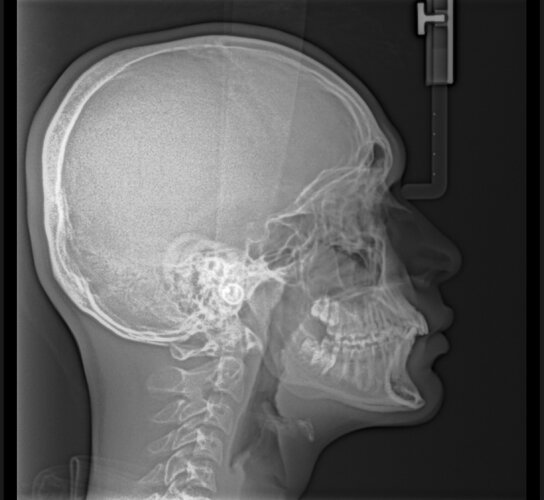

Can anyone read my Lateral Ceph x-rat? How recessed am I?

Also can you measure my SNA and SNB angles

Maxilla & mandible are recessed. You have a class II skeletal tendency(your upper jaw is ahead of the lower) & your chin(both the bone & soft tissue) is also recessed. Your upper & lower incisors are proclined though so it doesn't look so bad(known as a class II camouflage case). Your airway is fine, what's the ceph for bro?

Dang that’s brutal. What’s the solution for it? I’m 18 tho

Honestly could be worse, looks like you have light bimaxillary protrusion. Bimax, but just get braces for now as they'll need to fix your malocclusion.

Thanks. Yeah for now I’ll be getting braces, but idk why my ortho is saying my maxilla and mandible is ok?? What do you think about getting an MSE and braces after that? And are Damon braces better than Invisalign?

And do I need any hardmax other than Bimax? Or bimax will be enough to ascend me?

They say it's ok since they aren't affecting your function or airway, it's only harming you aesthetically.

All braces are better than Invisalign, as for MSE can't really tell from just your lateral ceph but if your palette is narrow and V shaped it's a good step.

For hardmaxx, if you can't afford or don't have the time for a bimax(18-36 months), you can always get a genio/chin implant & a rhino to fix an overly convex profile.